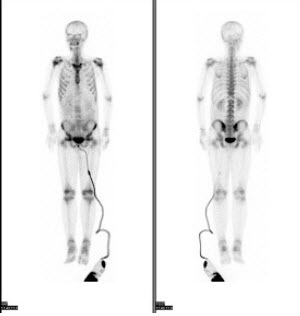

103、多项选择题

男性,62岁,膀胱印戒细胞癌术后半年,全身酸痛,对骨显像地描述正确的是()

A.颅骨多个“轮圈征”,提示有溶骨性病变

B.脊柱骨、肋骨弥漫性均匀性浓聚,肾脏不显影,是“超级骨显像”

C.提示中轴骨广泛转移癌

D.该患者预后不良

E.以上都不是

点击查看答案